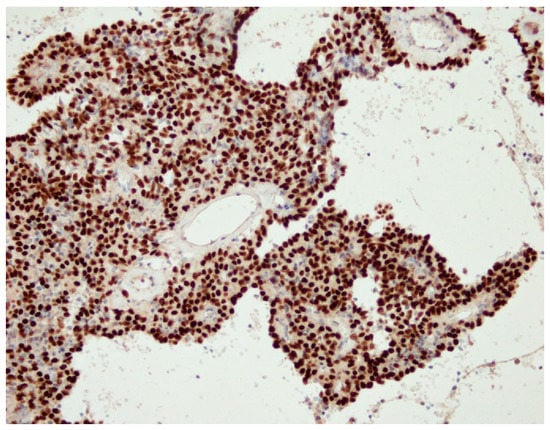

| Immunohistochemical finding | Surface cells: TTF1+, PanCK+ Round cells: TTF1+, Pan CK− All cells: PR+/ER− | Surface cells: TTF1+, PanCK+ Round cells: TTF1+, Pan CK- All cells: PR+/ER− | Surface cells: TTF1+, PanCK+ Round cells: TTF1+, Pan CK- All cells: PR+/ER+ | Surface cells: TTF1+, PanCK+ Round cells: TTF1+, Pan CK− All cells: PR+/ER− | Surface cells: TTF1+, PanCK+ Round cells: TTF1+, Pan CK− All cells: PR−/ER− | Surface cells: TTF1+, PanCK+ Round cells: TTF1+, Pan CK− All cells: PR−/ER− |